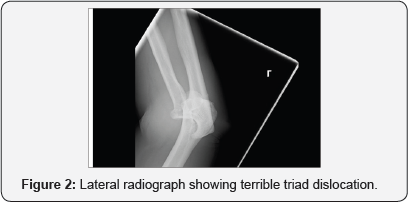

A 37 year old right hand dominant male sustained an injury when he came off a mountain bike at approximately 35 mph. His primary survey revealed no life threatening injuries but he had sustained bilateral closed upper limb injuries. On the left side he sustained a terrible triad injury of the elbow -i.e. a fracture dislocation of the ulnohumeral joint with an associated coronoid and radial head fracture (Figures 1 & 2). In addition he sustained an injury to the right distal radius which showed a dye-punch type intra-articular fracture. He was neurovascular intact throughout.

His elbow dislocation was reduced emergently in the operating room under general anaesthesia and a backslab in flexion was applied to his elbow that was documented to be very unstable by the treating surgeon. He was then admitted for observation and a specialist opinion was sought from a fellowship trained shoulder and elbow surgeon. In the interim CT scans of the elbow and wrist were performed for surgical planning purposes which illustrate the injuries in more detail (Figures 3 & 4).